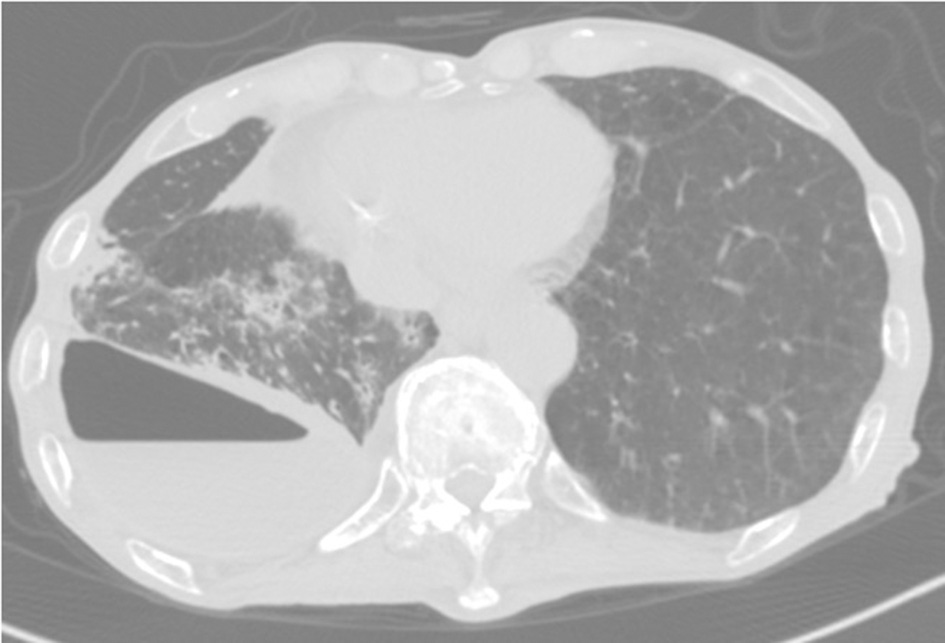

Eight months postsurgery, he lost his appetite. A CT scan showed increased pleural effusion with pneumothorax and new centrilobular nodular shadows in contact with the pleura (Figure 2). This time, the acid-fast bacterial smear test was positive. We diagnosed him with NTM pleurisy after excluding tuberculosis via PCR. However, we could not correctly identify the species using conventional methods such as AccuProbe (Gen-Probe Inc., San Diego, CA, USA), COBAS AMPLICOR (Roche Diagnostic, Tokyo, Japan), and a DNA-DNA hybridization assay (Kyokuto Pharmaceutical Industrial, Tokyo, Japan), although the growth and appearance of the colonies suggested M. fortuitum, a low-virulence organism. Table 1 shows the susceptibility results for this strain. We tried treating the pleurisy by drainage and single antibiotics, levofloxacin, and imipenem/cilastatin at the time of exacerbation. However, we could not control the effusion, and the patient died of aspiration pneumonia and CO2 narcosis.

Figure 2

CT scan showing pneumothorax and centrilobular nodular shadows with ipsilateral increasing pleural effusion.

In the NTM pleurisy pathogenesis, two possible mechanisms are considered. One is the direct extension of lung lesions into the pleura. The other is a hematogenous route (12). Because our patient's chest CT showed pneumothorax and centrilobular shadows contacting the thoracic cavity, which were previously unseen, M. mageritense pleurisy in our patient might have occurred via bulla rupture of a lung lesion. We also investigated the possibility that thoracic surgery might have caused the infection. However, his pleural effusion did not increase over several months postsurgery; therefore, we think this possibility was very low. Although we could not rule out disseminated NTM, the patient had no abnormal findings other than lung disease.